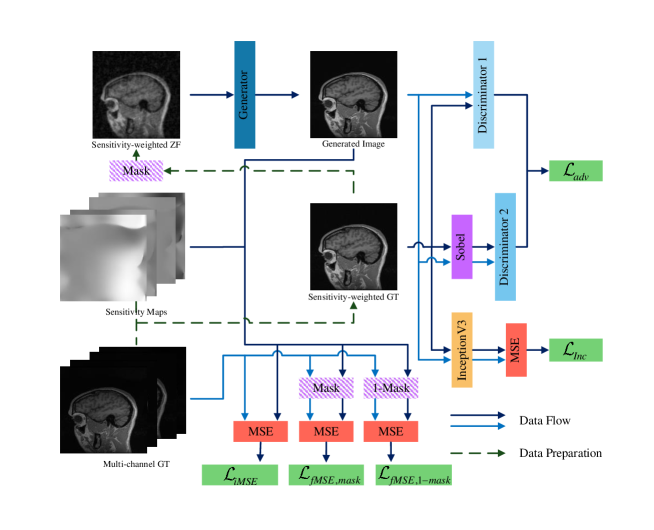

The overall architecture of the proposed PIDD-GAN for MR image reconstruction is shown in Fig. 1. Sensitivity-weighted ground truth is derived from the multi-channel ground truth , corresponding sensitivity map ( denotes the coil number) and sensitivity-weighted zero-filled image by undersampling . The generator produces the reconstructed MR image from . Two discriminators are used for the holistic image and the edge information, respectively.

Traditional GAN trains a single discriminator to compete against the generator. Although it improves reconstruction quality compared with other methods, only integral MR image properties are considered, without enhancing edge details. The current study proposes a dual discriminator GAN for edge information enhancement. The generated MR image and sensitivity-weighted MR ground truth are fed into discriminator for holistic image reconstruction. We use the Sobel operator to extract the edge information from MR images, and input edge information for the reconstructed image and ground truth into . Thus, both holistic image information and edge details can be simultaneously reconstructed.

2.5 Loss Function

This study introduces content loss to train the generator for better reconstruction quality. Content loss comprises pixel-wise mean square error (MSE) loss ; the frequency MSE loss and ; and the perceptual InceptionV3 loss . Pixel-wise MSE loss can be defined as

where is the sensitivity map of the coil. is used to reduce the artefact between the generated image and the ground truth. However, optimisation with only would make the reconstructed image lack coherent image details. Therefore, frequency MSE loss is applied to train the generator in k-space.

The frequency MSE loss can be defined as

where eliminates differences between undersampled generated images and undersampled k-space measurements . is used to minimise the differences between the interpolated data based on the generated image and the unacquired k-space data .

In addition, the perceptual Inception V3 loss can be defined as

where denotes the Inception V3 network (Szegedy, ). is used to optimise the perceptual quality of reconstructed results.

The adversarial loss is defined as

Hence, the total loss can be described as

where , and are coefficients balancing each term in the loss function.